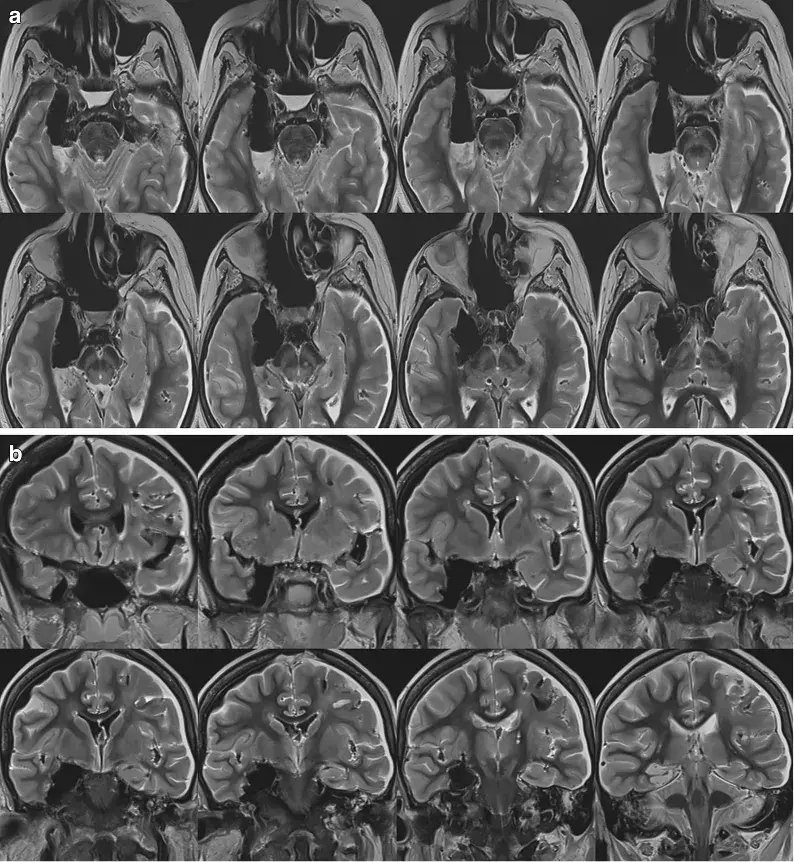

经外侧裂选择性切除海马杏仁核治疗mtle的疗效

图片尺寸1280x1242

图片尺寸2004x535